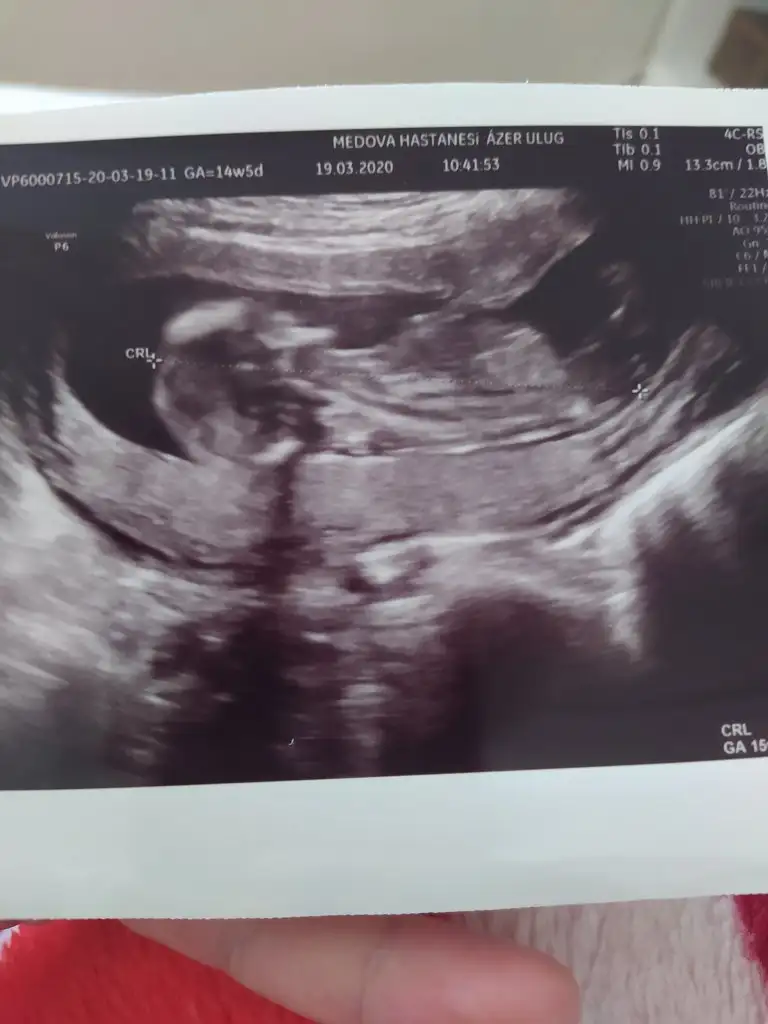

Merhaba yeni uyeyim elimde 7 haftalik karindan 10 haftalik alltan ulturason goruntusu var cinsiyet tahmini yapabilirmisiniz acaba şimdiden teşekkurler ilk resim 7 hafta karin son resim 10 haftta altan bakildi.

Banada bakarmısınız şimdi ikili testten çıktım doktor erken dedi soylemedi çok merak ediyorum 12 haftalik

Merhabalar, ctesi ikili test icin gittim 11+6 idim. Suana kadar hep haftayla uyumlu giderdi sat. Ama bu sefer 12+6 cıktım. Yine de cinsiyet yorumlar mısınız? Gec mi kaldım? Bir de doktor tahminini söyledi ama emin değil. Kafanız karışmasın diye en son söyleyeceğim.